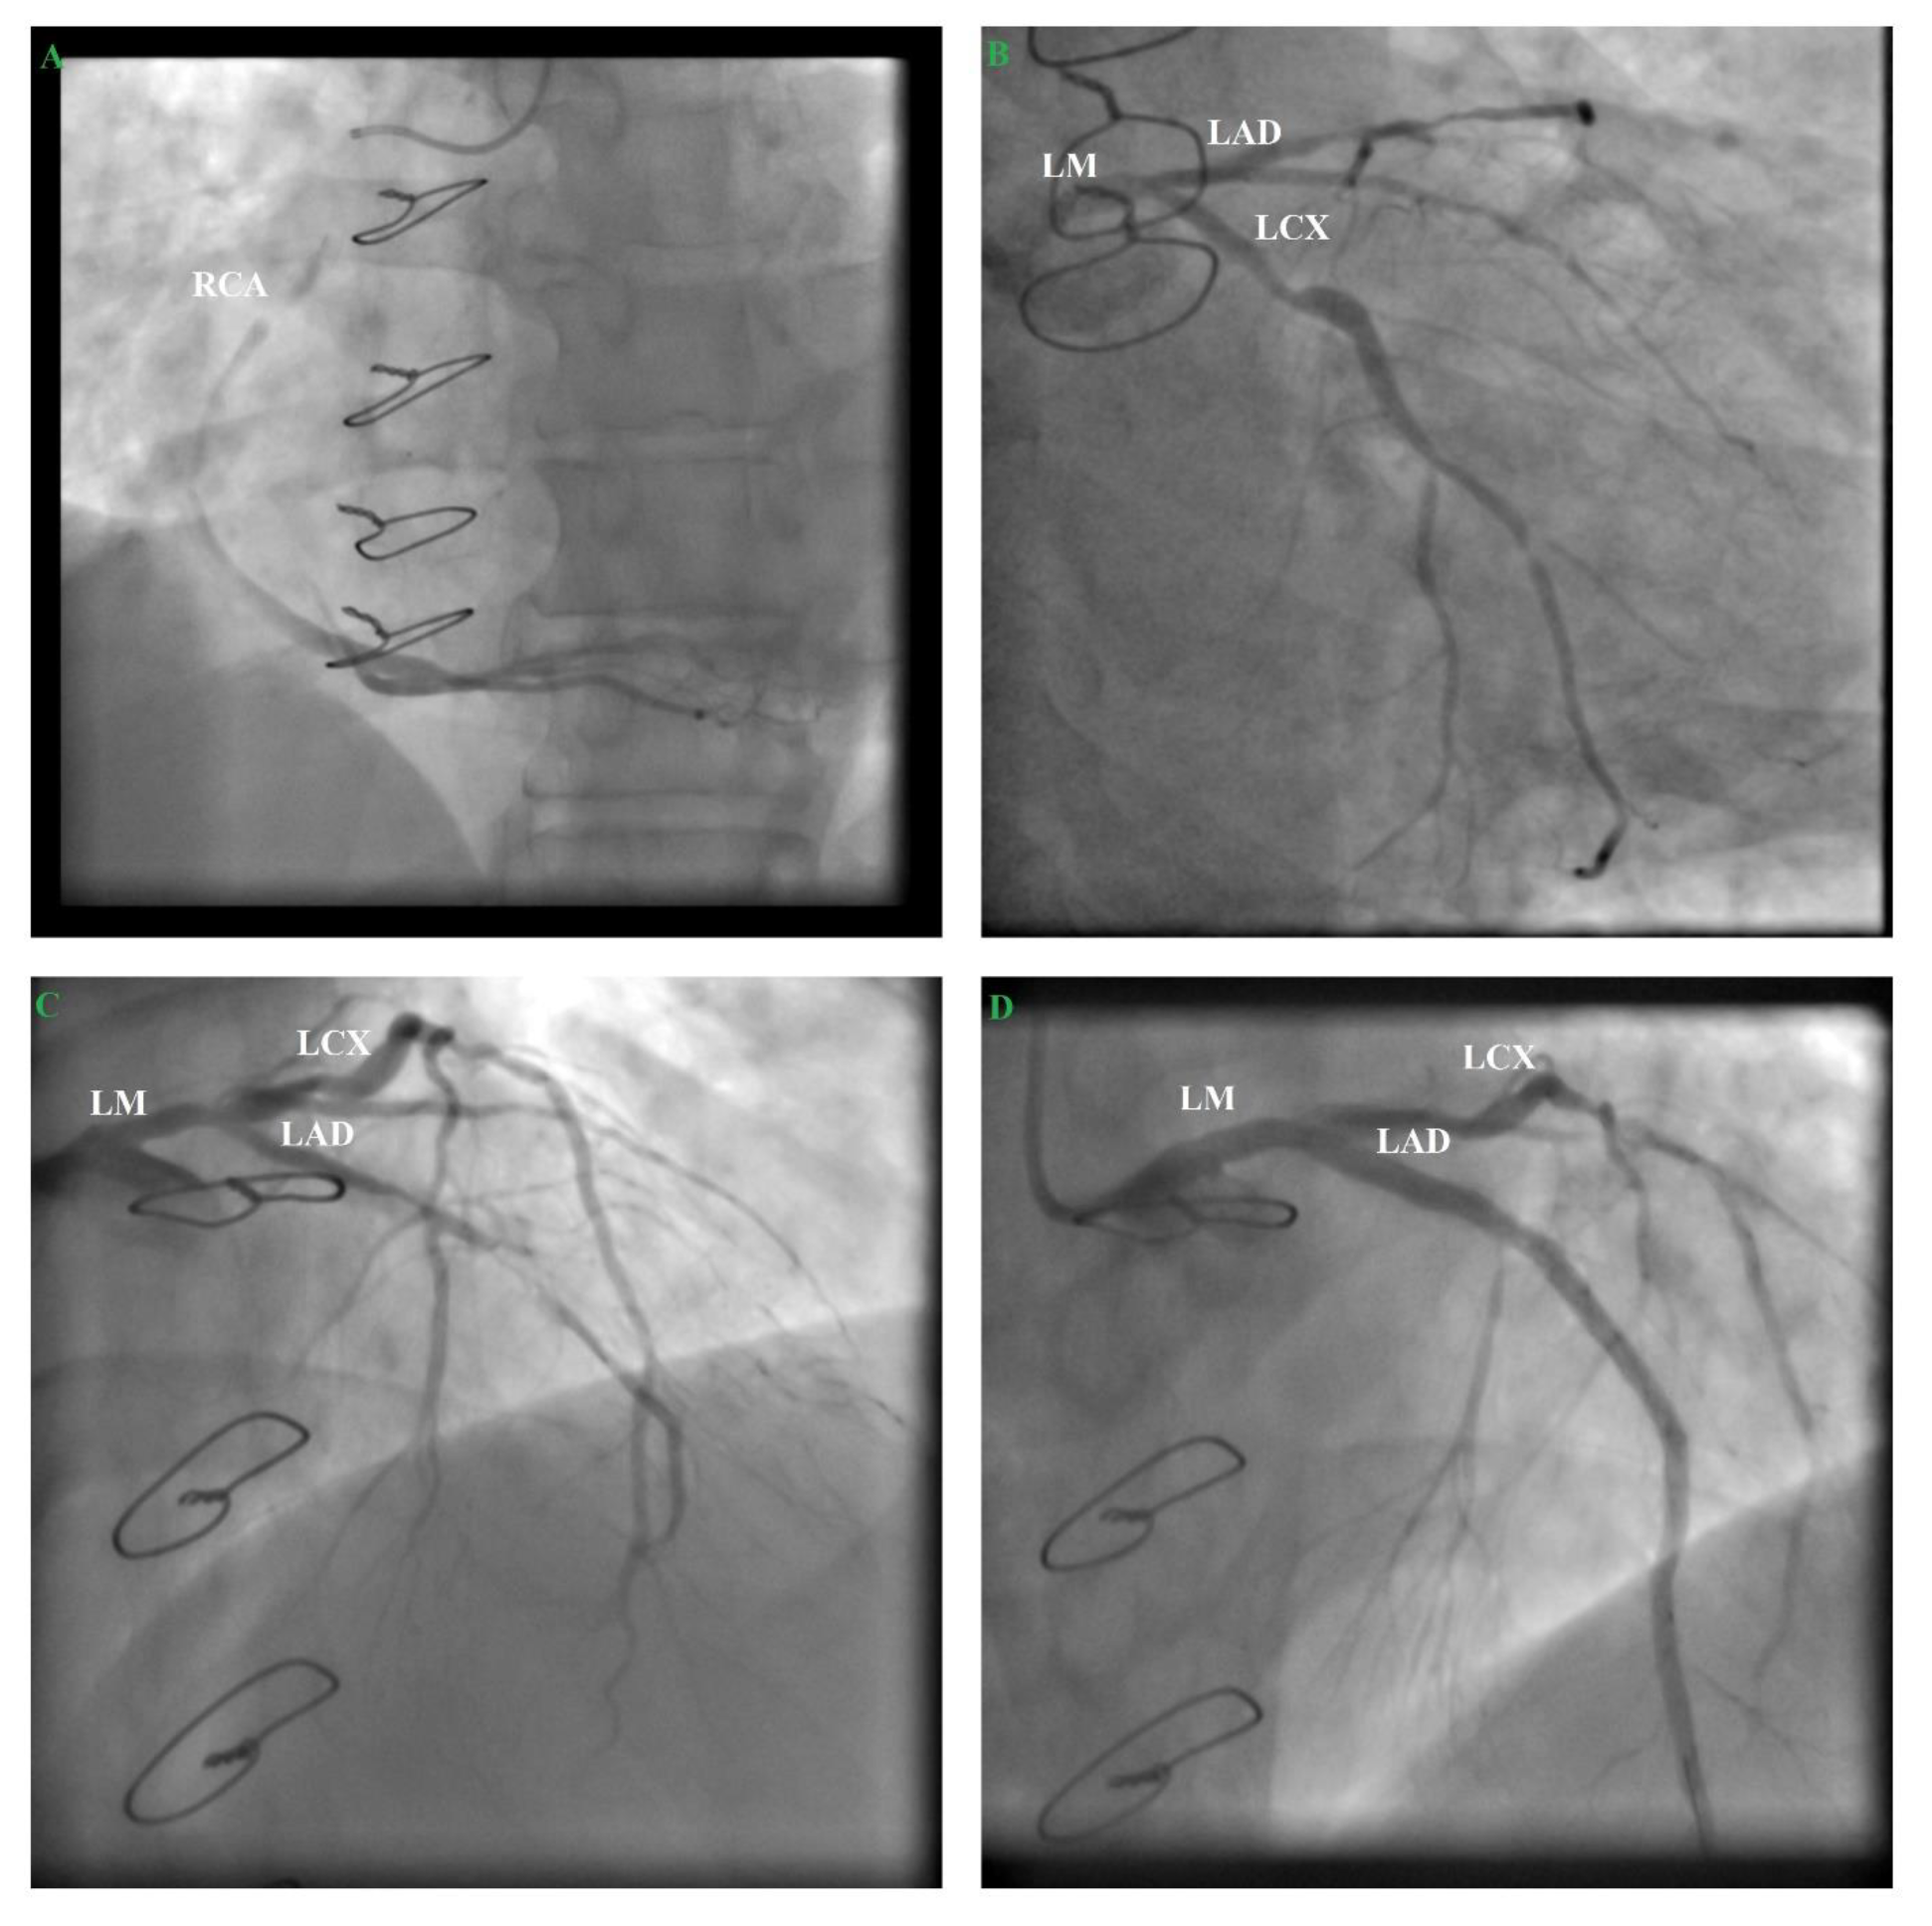

2. Case Report